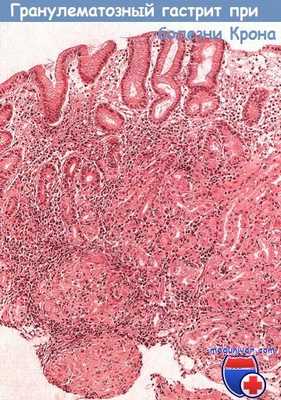

Диагноз гранулематозного гастрита ставят путем исключения, так как изменения желудка при данном заболевании и при туберкулезе, саркоидозе, болезни Крона схожи. Однако системные проявления здесь отсутствуют, а больных, как правило, беспокоит только диспепсия.

Макроскопически определяют изъязвления, инфильтрацию и утолщение слизистой оболочки, приводящее к сужению пилорического отдела или изменениям, подобным инфильтративной форме рака [пластический линит (linitisplastica)]. Гистологически в слизистой оболочке желудка определяют гигантоклеточные гранулемы с признаками сопутствующего гастрита или без них.

Микроскопическая картина гранулематозного гастрита при болезни Крона с поражением верхних отделов желудочно-кишечного тракта.

В области антрального отдела желудка определяются четкие неказеозные гранулемы, окруженные участками хронического воспаления в собственной пластинке слизистой оболочки